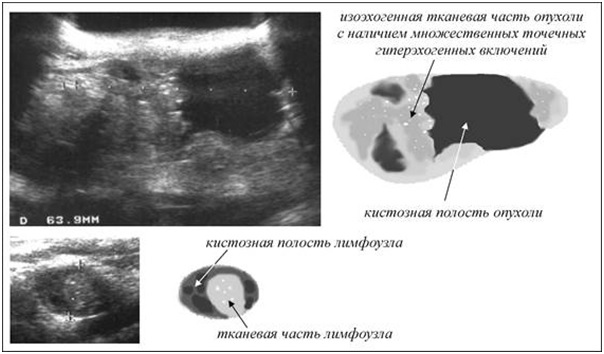

Если природа включения является злокачественной, то по мере прогрессирования процесса (увеличения опухолевого образования), проявляется такая симптоматика, как наличие в очаге анэхогенных, гипоэхогенных или гиперэхогенных образований.

Так это выглядит на экране монитора.